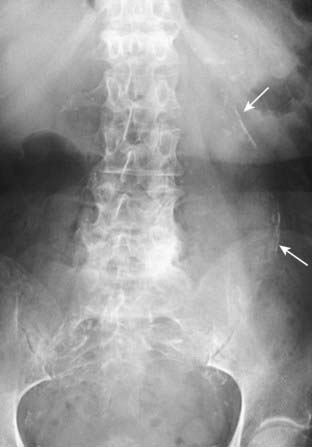

Figure 16-7 Renal calculus.

There is a small calcification (solid black arrow) that overlies the shadow of the left kidney (solid white arrow) on this close-up of a conventional abdominal radiograph. Although the stone is too small to recognize lamination, its location suggests a renal calculus. Because of its greater sensitivity, a CT stone search has essentially replaced conventional radiography for the identification of renal and ureteral calculi.